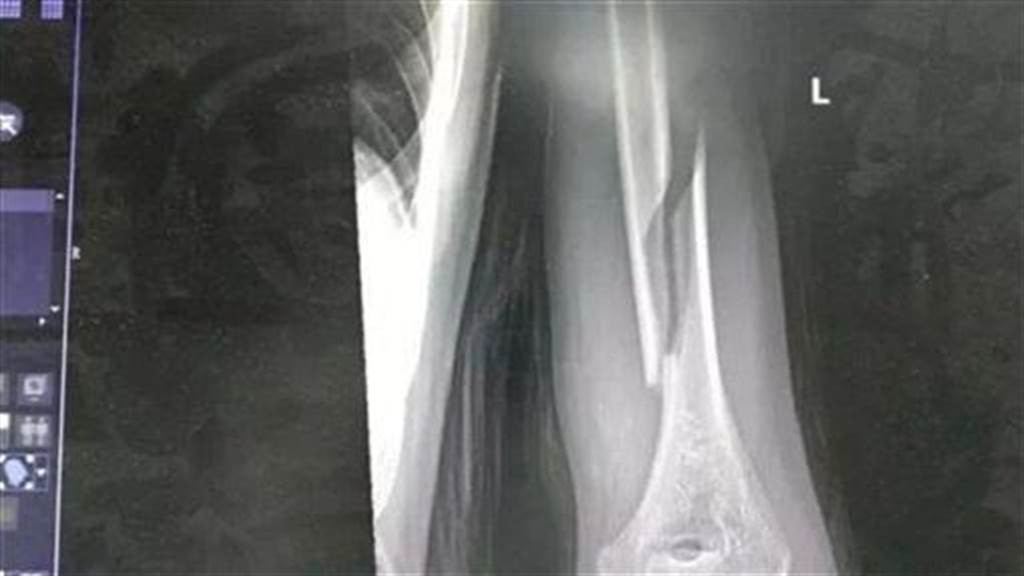

Ngay sau đó, anh đã đưa con trai đến bệnh viện để cấp cứu. Tại bệnh viện, sau khi chụp X-quang, các bác sĩ cho biết, trường hợp gãy tay của con trai anh rất nghiêm trọng.

Theo các bác sĩ, xương cánh tay là bộ phận cứng rắn nhất trên cơ thể con người. Thế nhưng lại bị vặn gãy, hơn nữa gãy kiểu xoắn ốc, uốn lượn rất kỳ quái, rất khó điều trị, phải lập tức phẫu thuật.